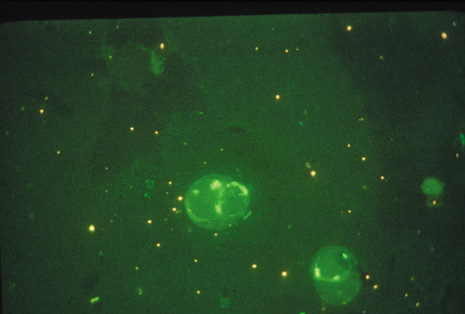

Although keratocentesis had been advocated historically as a treatment for active uveitis, it lost the attention of ophthalmologists until 1919, when Bruckner3 first examined the aqueous humor for diagnostic purposes. Laboratory techniques were revolutionized in the 20th century in areas such as: (a) evaluating very small aliquots of fluid (0.2 to 0.3 mL of aqueous or vitreous), and (b) identifying specific microbial organisms and the predominance of other cell types, antibodies, and proteins in these fluids (Figs. 1, 2, 3, 4, 5, and 6). These advancements have led to the development of diagnostic paracentesis for sight-threatening ocular inflammations that are difficult to diagnose. Witmer4 and O'Connor5 have provided strong evidence that samples of the aqueous humor reflect the antibody-producing capabilities of the iris and ciliary body, particularly when more specific antibody per unit of gamma globulin can be found on the aqueous humor than in the blood of the same patient.6–8 These determinations may be highly significant when one considers the fact that diseased tissue is being bathed in an antibody-containing fluid that is elaborated locally. For instance, in the case shown in Figure 1, the immunofluorescent antibody titer to toxoplasmosis is four times greater in the vitreous aspirate at the time of vitrectomy for repair of retinal detachment than in the plasma. These same considerations have long been recognized in syphilis of the central nervous system, wherein specific antibodies may be present in the cerebrospinal fluid but not in the blood. This is also the case with an unusual presentation of ocular coccidioidomycosis9 or toxocariasis.

Precise identification and culture of bacterial and fungal pathogens from both the aqueous humor and the vitreous fluid can be obtained. Gram's stain and Giemsa's stain smears of centrifuged specimens from the aqueous humor and the vitreous humor frequently demonstrate the bacterial or fungal causative agent. Attempts to isolate bacteria and fungi and to identify them on Gram's stain or Giemsa's stain smears have been most rewarding in the following cases: (a) postoperative endophthalmitis, (b) infection after a penetrating injury of the eye, (c) drug abuse patients with endogenous endophthalmitis (Figs. 21, 22, 23, 24, and 25), (d) patients receiving hyperalimentation, and (4) patients who are immunocompromised as a result of exogenous immunosuppressive agents.

Studies have demonstrated the usefulness of ocular paracentesis for the identification of ocular infections in order to implement sight-saving treatment.10–16 Even acid-fast bacilli and viruses may be diagnosed in this fashion when emergency dictates (see Fig. 5).17 It is recommended that diagnostic paracentesis be performed in all cases of postoperative endophthalmitis, and it is safe to perform the postoperative procedure in the operating room with the safety of vitrectomy surgery. Further, any patient older than 65 who presents with a deteriorating uveitis (usually with vitreitis as the predominant infiltrate) of undetermined etiology should undergo paracentesis of the vitreous to rule out reticulum cell sarcoma (large cell lymphoma).18 Similarly, any patient suspected of being an intravenous drug abuser who presents with an endogenous endophthalmitis or uveitis should undergo diagnostic paracentesis to avoid allowing an intraocular infection to be borne by the bloodstream.19,20